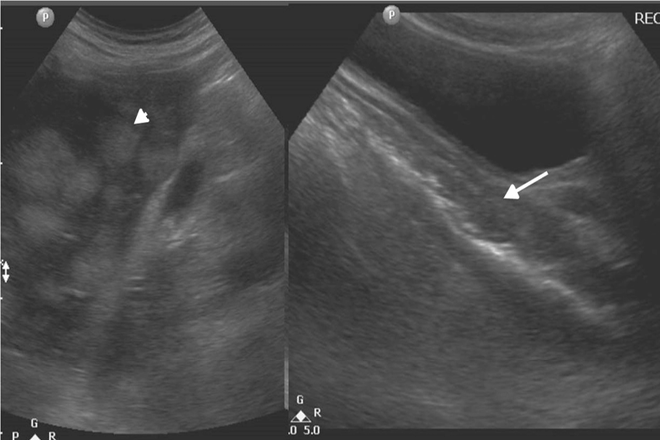

Ecográficamente se observa una masa hepática hipo o hipercoica, en el doppler muestra anastomosis arteriovenosas, con el paso de tiempo se hace una mayor ecogenicidad.

Ecográficamente se observan bien delimitados hipercoicos con refuerzo acústico, son de ecogenicidad heterogénea, con el uso del doppler se observan vasos en la periferia.

Ecográficamente, se observa una masa quística, puede ser de múltiples quistes con tabiques gruesos, dando la apariencia de “queso suizo”.

Ecográficamente, es una lesión solitaria de bordes definidos, se observa una masa ecogénica con zonas de sombra acústica, que son calcificaciones y áreas hipoecoicas que reflejan zonas de hemorragia o necróticas.

Ecográficamente, puede ir desde ecogénico hasta anecoico, dependiendo del estadio. El absceso en las primeras etapas suele ser sólido, conforme llega a la necrosis y licuefacción el absceso de observa de bordes irregulares con contornos delimitados. Las lesiones que son más ecogénicas se deben a la presencia de gas dentro de la cavidad del absceso, este gas produce sombra acústica o reverberaciones. Cuando las lesiones son hipocoicas representan necrosis y licuefacción, con el doppler muestra flujo en la periferia.

Se trata de recién nacido a término, obtenido por vía cesárea, liquido amniótico con meconio, con antecedente de asfixia perinatal, el cual requirió reanimación e intubación. Durante su internamiento presenta alteración en pruebas de función hepática y hepatomegalia, se le realiza un usg es donde se observa a nivel de hígado una masa de 40×30 mm de aspecto heterogéneo, con vascularidad periférica, se hizo diagnostico de probable absceso hepático, vesícula biliar distendida con barro biliar e hidronefrosis. Se decidió administrar antibioticoterapia durante 15 días, y seguimiento ultrasonográfico semanal, en donde se observó el decremento de dicha masa, confirmando absceso hepático.